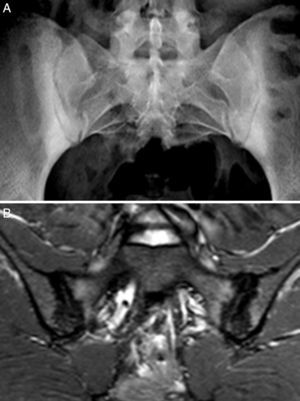

Case no. 3: a 50-year-old woman who had been diagnosed with ankylosing spondylitis 3 years earlier, with bilateral sacroiliitis on plain radiography and HLA-B27 positivity. She had severe refractory, disabling, inflammatory low back pain, with an insufficient response to nonsteroidal anti-inflammatory drugs, and difficult management due to the coexistence of obesity, spondyloarthrosis, hypertension, chronic elevations of transaminase levels, diabetes mellitus, autoimmune hypothyroidism and diarrhea. The pain confined her to a life of crutches and wheelchairs, with dependence on others for her personal care. Ileocolonoscopy with biopsies of ileum and colon was normal. Magnetic resonance imaging of sacroiliac joints revealed marked bone marrow edema, demonstrating sacroiliitis. Serological screening for CD was negative; HLA typing revealed homozygosity and absence of DQ2 and DQ8. Duodenal biopsy was proposed to her, but she opted for trying the GFD without duodenal biopsy. Her response to the GFD and vitamin D supplements was very good, with remission of the disabling low back pain and diarrhea after 7 months. Mechanical low back pain and asthenia persisted. Milk and dairy products were eliminated from her diet and the asthenia improved. Magnetic resonance imaging of the sacroiliac joints performed after 17 months of follow-up showed remission of bone marrow edema (Fig. 3). She had returned to a normal active life and to work. She did not ingest gluten again.

These 4 patients have axial spondyloarthritis, 2 of them with ankylosing spondylitis and 1 with psoriatic spondyloarthritis. They are sensitive to gluten, with a clear clinical response to a GFD, despite the fact that CD had been ruled out. In 2 cases, the patient has a first-degree relative with CD. The improvement in chronic low back pain has been highly relevant, to the extent that the clinical symptoms resolved. In 1 case, after a long follow-up period, MRI of the sacroiliac joints demonstrated remission of the edema. Moreover, in the 3 patients who had been exposed to gluten, exposure was followed by clinical recurrence. It is improbable that a clinical improvement like that described here be incidental or due to a placebo effect. The observation of intraepithelial lymphocytosis together with the clinical course supports the concept of enteropathic spondyloarthritis secondary to NCGS. Fig. 4 shows the duodenal biopsies from cases 1, 2 and 4, demonstrating the increased lymphocytes in the intestinal epithelium.